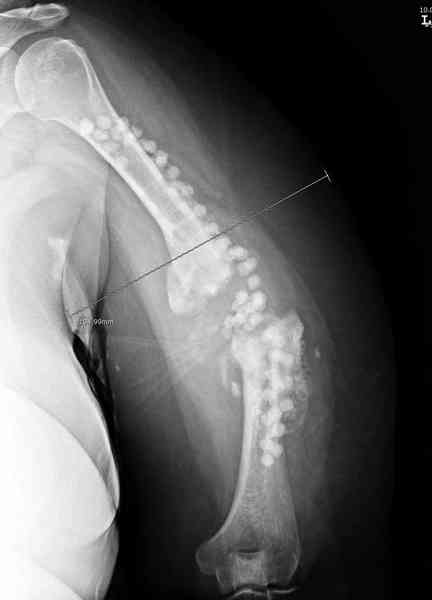

Помогите, пожалуйста, определиться с тактикой!Поступил больной с ложным суставом плечевой кости... Перелом был 2 года назад. Лечился в аппарате 8 месяцев, консолидации не произошло. В феврале 2007 выполнена костная аутопластика, фиксация пластиной (на базе одной из ИК). Сейчас сохраняется ложный сустав, плечо укорочено на 3 см, контрактура обоих смежных суставов, атрофия мышц плеча и плечевого пояса справа. Явлений остеомиелита не отмечалось. Больной - осужденный, сидеть ему до 2012 года.

Когда разбирался случай на сайте, и у нас была больная с похожей патологией, ложный сустав после поперечного перелома, леченного год назад где-то и кем-то в другом месте.